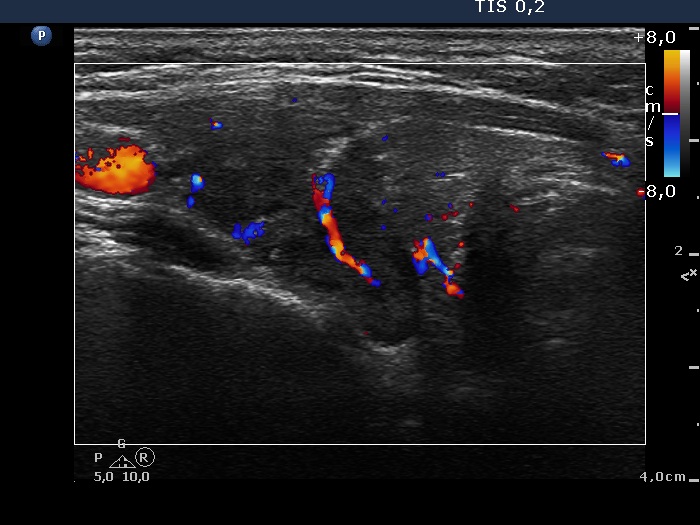

Discrete lesion or nodule in Hashimoto's thyroiditis - case 6 (8) (ultrasonographic picture 3)

Right lobe, transverse view, color Doppler mode. A large vessel runs in the central part of the lobe.